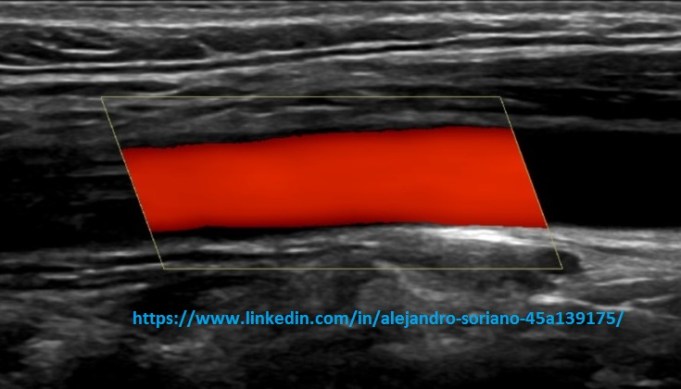

Se coloca un ROI que se superpone a la imagen 2D dándonos a conocer la distribución de los vasos respecto al tejido. Nos permite conocer la velocidad promedio del volumen de la muestra y su dirección.

Está establecido que los flujos que se aproximen a la sonda tengan colores rojizos, mientras que los que se alejan son colores azulados.

Es muy útil para el estudio de los vasos, pero vital para conocer la vascularización de estructuras sospechosas de patología, desde tendinopatías hasta lesiones tumorales.